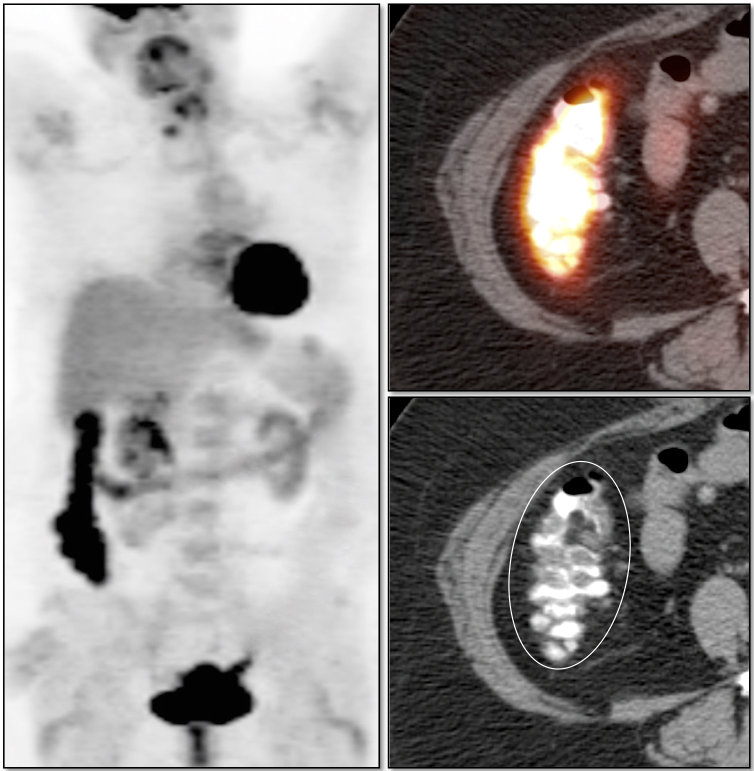

• Beware the small rectal cancer!  As the ano-rectal region frequently demonstrates intense physiologic uptake, it is very easy to overlook a rectal malignancy, especially if it is an incidental finding.  To avoid this error, always evaluate the rectum carefully on the sagittal whole body images.  It is shocking to see how readily apparent a rectal cancer can be on these images, yet so easily overlooked in the axial plane.

• Always evaluate the colonic anastomosis on a follow up exam, as it is a occasional site of recurrent disease.